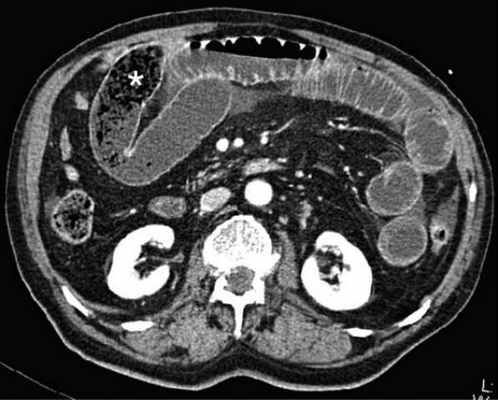

Осложнённая форма (чаще всего в результате странгуляции)

Для странгуляции тонкой кишки характерны утолщение стенок кишечника, васкулярные нарушения и выраженные патологические изменения в брыжейке и в брюшной полости. Диагностические находки включают в себя:

-утолщение стенки кишки циркулярного типа. Важно помнить, такой тип утолщения стенок тонкой кишки при непроходимости как правило связан с сосудистыми нарушениями;

-нарушение нормального контрастного усиления стенок кишки. Изменения варьируют от гиперконтрастирования до полного отсуствия контрастного усиления. Различные варианты этих изменений между описанными выше крайностями могут наблюдаться одновременно в разных сегментах тонкой кишки. Полное отсутствие усиления означает артериальный рефлекторный спазм и свидетельствует в пользу тяжести поражения;

-петля с утолщенными стенками теряет свою эластичность и становится ригидной, вытянутой;

-пристеночный пневматоз тонкой кишки, в особо тяжелых случаях появляются интрамуральные пузырьки газа;

-появление патологических плотностей в брыжейке в виде распространяющихся матовых инфильтратов и тяжистости за счет кровоизлияний в жировые ткани;

-застойные изменения сосудов брыжейки. Сначала диаметр сосудов увеличивается, но со временем наступает рефлекторный артериальный спазм, брыжейка будет выглядеть с обеднённой васкуляризацией. Сосуды сужены или с полностью коллабированным просветом;

-при заворотах нарушается нормальная сосудистая анатомия брыжейки. Сосуды как бы закручиваются вокруг оси заворота и тянут за собой измененный брыжеечный жир- по типу раковины улитки или торнадо. Для большей наглядности представьте себе кусок расправленной ткани на столе, которую вы прижали пальцем и начали закручивать не отрывая ваш палец от стола. На КТ сканах часто можно увидеть характерный признак конусовидной спирали (whirl sign);

-свободная жидкость в карманах брыжейки и в брюшной полости. Иногда жидкость может быть повышенной плотности за счет геморрагического компонента.

примеры странгуляционной осложнённой непроходимости с характерными изменениями в брыжейке, внутрибрюшинном жире, утолщением стенок тонкой кишки и нарушением контрастного усиления.